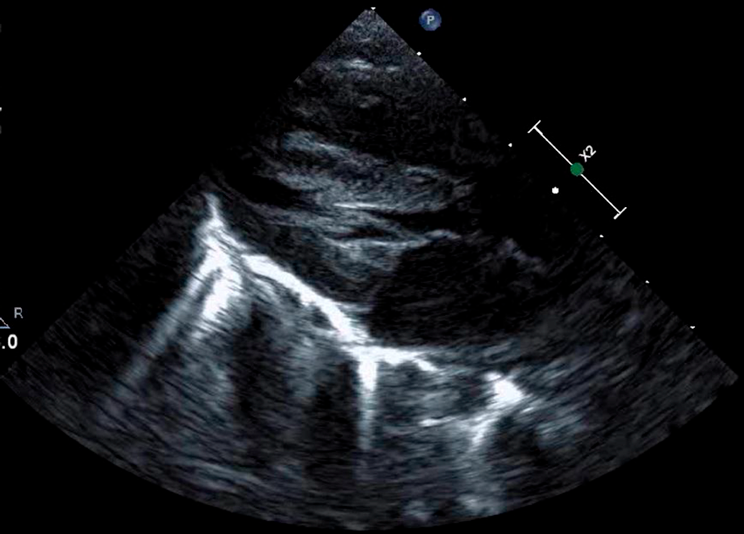

肥大型心筋症を合併した心房中隔欠損症に対して開窓付閉鎖術が奏功した1例Fenestrated Closure of an Atrial Septal Defect for Left Ventricular Diastolic Dysfunction in an Early Infant with Hypertrophic Cardiomyopathy